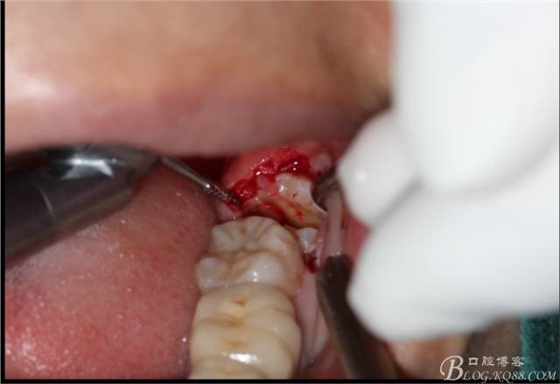

分冠完成

取出阻力部分冠

在取出阻力冠后,嘗試性看能取出全部的牙體不,就是取不出也能整體撬動牙根。